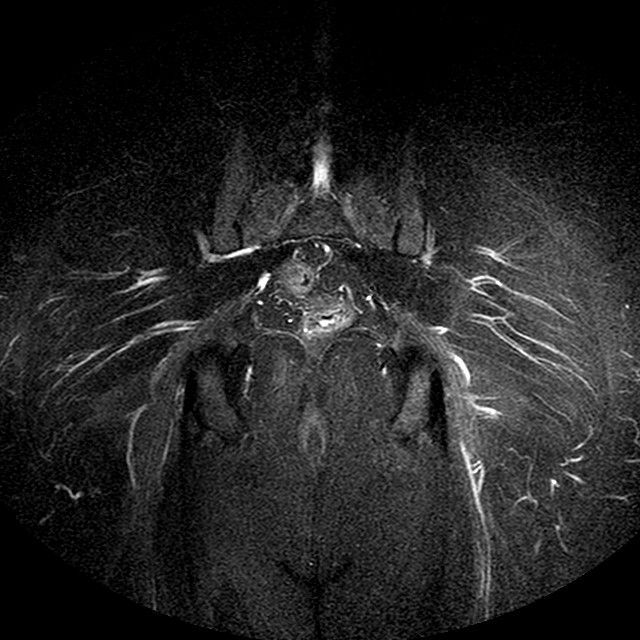

STIR

Evidenti e simmetriche alterazioni osteofitosiche in regione coxo femorale con riduzione delle rime articolari. Degenerazione completa del cercine glenoideo. Non attuali segni di versamento articolare. Non segni di edema osseo che escludono attuale algodistrofia od osteonecrosi. Lieve e simmetrica riduzione del trofismo della muscolatura glutea.